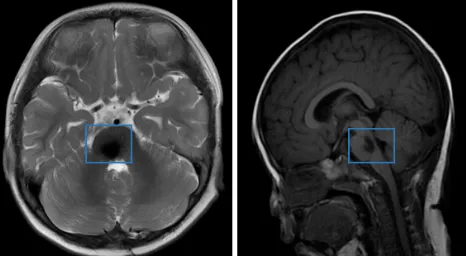

急诊医生的凝重表情证实了家长的担忧。MRI检查结果显示:第四脑室底部存在占位性病变。